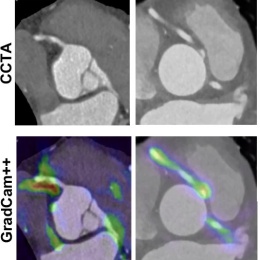

„Vor allem die Scannertechnologie hat sich weiterentwickelt, aber auch die Nachbearbeitung“, sagte er. „Und dieser gesamte Prozess wird durch künstliche Intelligenz beschleunigt und verbessert.“ Unter den vielversprechenden CT-Anwendungen für KI hob der Experte Lösungen hervor, die die Variabilität zwischen einzelnen Untersuchern reduzieren7, das prognostische Potenzial koronarer Plaques und Entzündungsaktivität im Fettgewebe (fat attenuation index; FAI) nutzen8,9,10, und seltene Krankheitsbilder wie Anomalien der Koronararterien erkennen.11